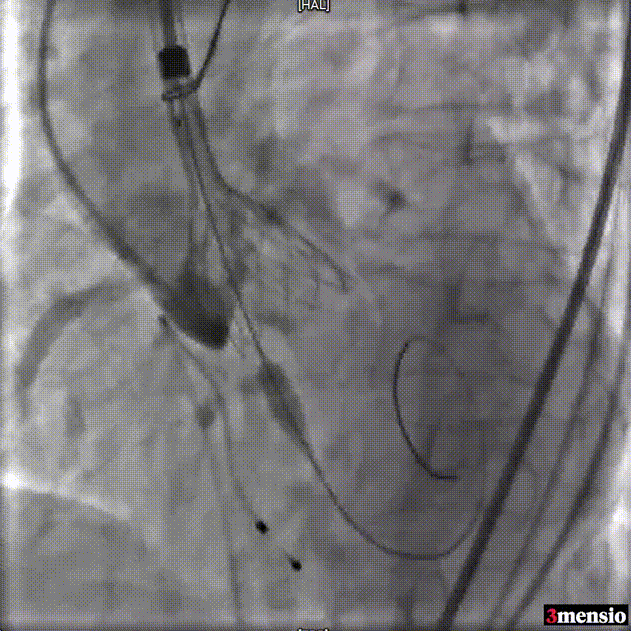

瓣膜释放至工作位评估

瓣膜脱钩

25mm球囊后扩

瓣膜最终形态